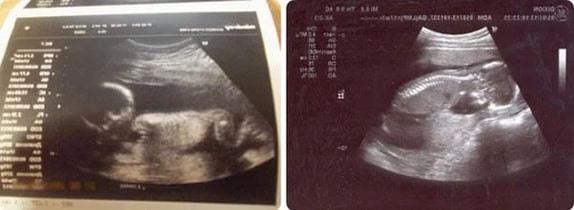

15 Haftalık İkiz Gebelik Ultrason Görüntüleri

16 Haftalık İkiz Gebelik Ultrason Görüntüleri